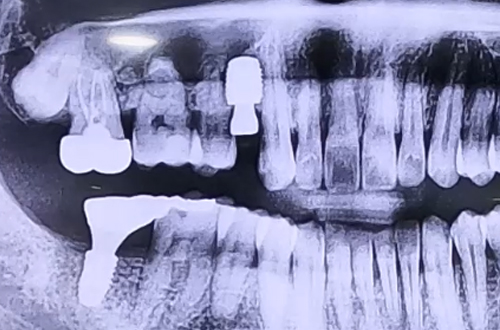

AFTER

본원에서는 다양한 종류의 임플란트를 취급하고 있기 때문에 어떤 임플란트를 사용했든 중단된 치료를 이어서 마무리할 수 있어 꼭 맞는 보철을 제작하여 마무리를 해 드렸습니다.

잇몸이 충분히 단단해진 뒤 뼈이식과 함께 골유착에 용이한 임플란트를 선택하여 진행했어요.

임플란트가 단단히 굳고 보철이 완성되면 진료일지를 통해 다시 찾아뵙겠습니다. ^^